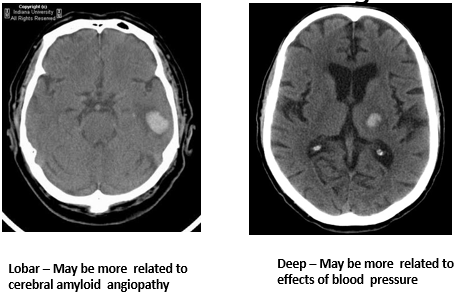

How is small vessel disease classified?

6 types:

• Type 1 - arteriosclerotic (age/risk factor related)

• Type 2 - sporadic and hereditary cerebral amyloid angiopathy (CAA)

What are causes of primary intracerebral haemorrhage?

Hypertension and amyloid angiopathy